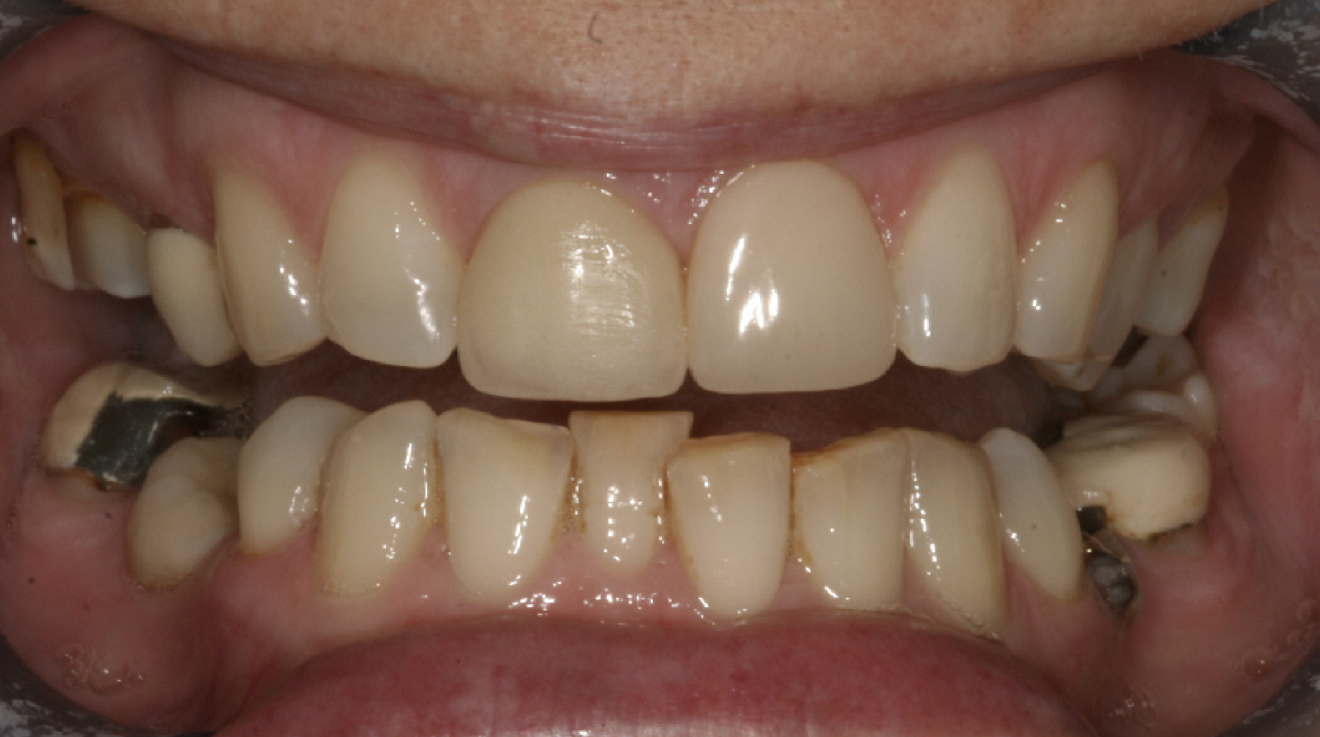

A 48-year-old female patient came to see me in 2004. The patient initially presented because she was unhappy with her two discoloured maxillary central incisors (Fig. 1). She also had chipping and wear of the mandibular teeth and broken posterior bridgework. Her “bite” also felt uncomfortable (Fig. 2).

Fig. 1: 2004—discoloured maxillary central incisors.